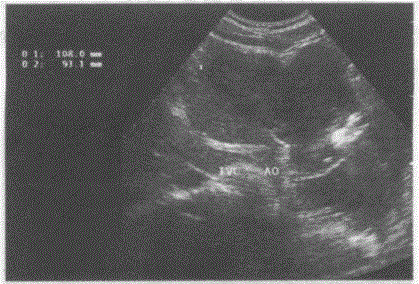

问题 临床资料:女,34岁,自述进食后上腹部不适。 超声综合描述:腹主动脉下腔静脉前方可见10.1cm×9.3cm形态不规则低回声,边界清晰,内回声不均匀,肝左叶受其推挤形态失常。 超声提示:

选项 A.胰腺癌 B.胃平滑肌肉瘤 C.肝癌 D.腹腔肿大淋巴结

答案 B